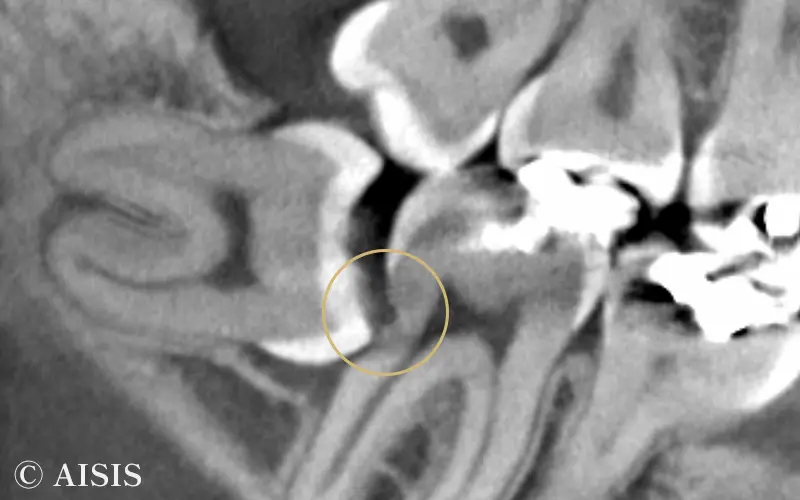

例えば、レントゲン写真は、横向きに生えている親知らずです。

親知らずが横向きに生えていることによって、手前の歯と親知らずが密接している箇所が黒ずんでいるのを確認頂けると思います。この部分が虫歯になっています。